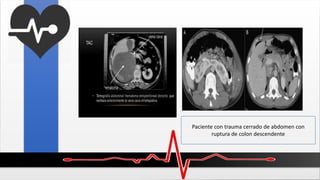

Paciente con trauma cerrado de abdomen con

ruptura de colon descendente

Paciente con traumacerrado de abdomen con ruptura de colon descendente